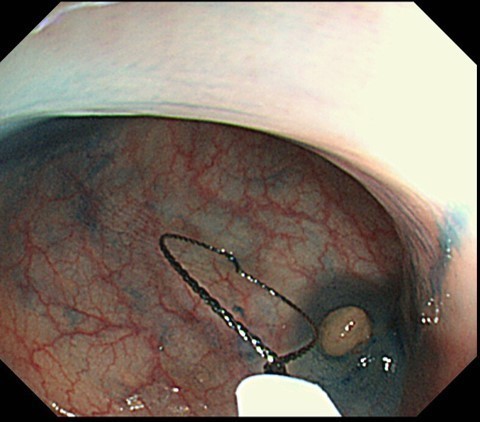

腸の中を見る大腸検査は 検査専用の下剤できれいになった大腸の中を内視鏡で観察します。腸の奥までカメラを入れていく内視鏡操作はもちろんのこと、何よりも病変の発見と診断そしてその病変の治療高度な技術が必要です。技術によって検査・治療の質が大きく変わるのが内視鏡検査です。

当院では国立がんセンター中央病院で行ってきた豊富な技術をいかして、確実に診断・治療を行います。また大腸ポリープを発見された場合、同時に検査も治療も行うことができます。そのため大腸内視鏡では軽い鎮静剤を使用し、治療にもすぐに対応できるようにして、優しい検査を行っています。

当クリニックでは大腸ポリープ・病変発見時に一度で検査・治療を行うことができます。

大腸内視鏡を行ってもポリープが見つかると、あらためて別の病院でもう一度下剤をのみ直し内視鏡治療を受ける必要がある施設もあります。一度で治療までできることは体力も時間も金銭的にも負担が少なくなります。

少しでも検査を受けられるみなさんの負担が少なくなるよう工夫し、当クリニックでは大腸ポリープ・病変発見時に一度で検査・治療を行うことができ、治療のあとゆっくり休むことができる体制を整えております。